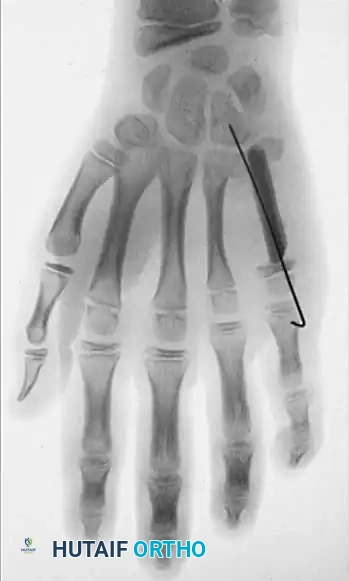

Surgical Excision and Recurrence

Excision is notoriously difficult. These tumors frequently wind in and around the flexor tendons, their synovial sheaths, digital nerves, and occasionally the extensor mechanism, sometimes encompassing three-fourths of

Associated Surgical & Radiographic Imaging